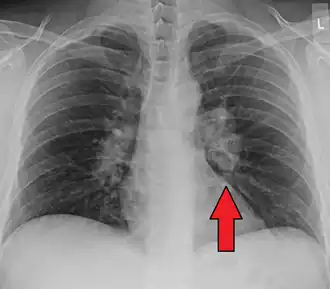

| Chest X-ray showing the typical nodularity of sarcoidosis, predominantly in the hila of the lungs. | |

Chest radiograph changes are divided into four stages:[104]

- bihilar lymphadenopathy

- bihilar lymphadenopathy and reticulonodular infiltrates

- bilateral pulmonary infiltrates

- fibrocystic sarcoidosis typically with upward hilar retraction, cystic and bullous changes

Although people with stage 1 radiographs tend to have the acute or subacute, reversible form of the disease, those with stages 2 and 3 often have the chronic, progressive disease; these patterns do not represent consecutive "stages" of sarcoidosis. Thus, except for epidemiologic purposes, this categorization is mostly of historic interest.[28]